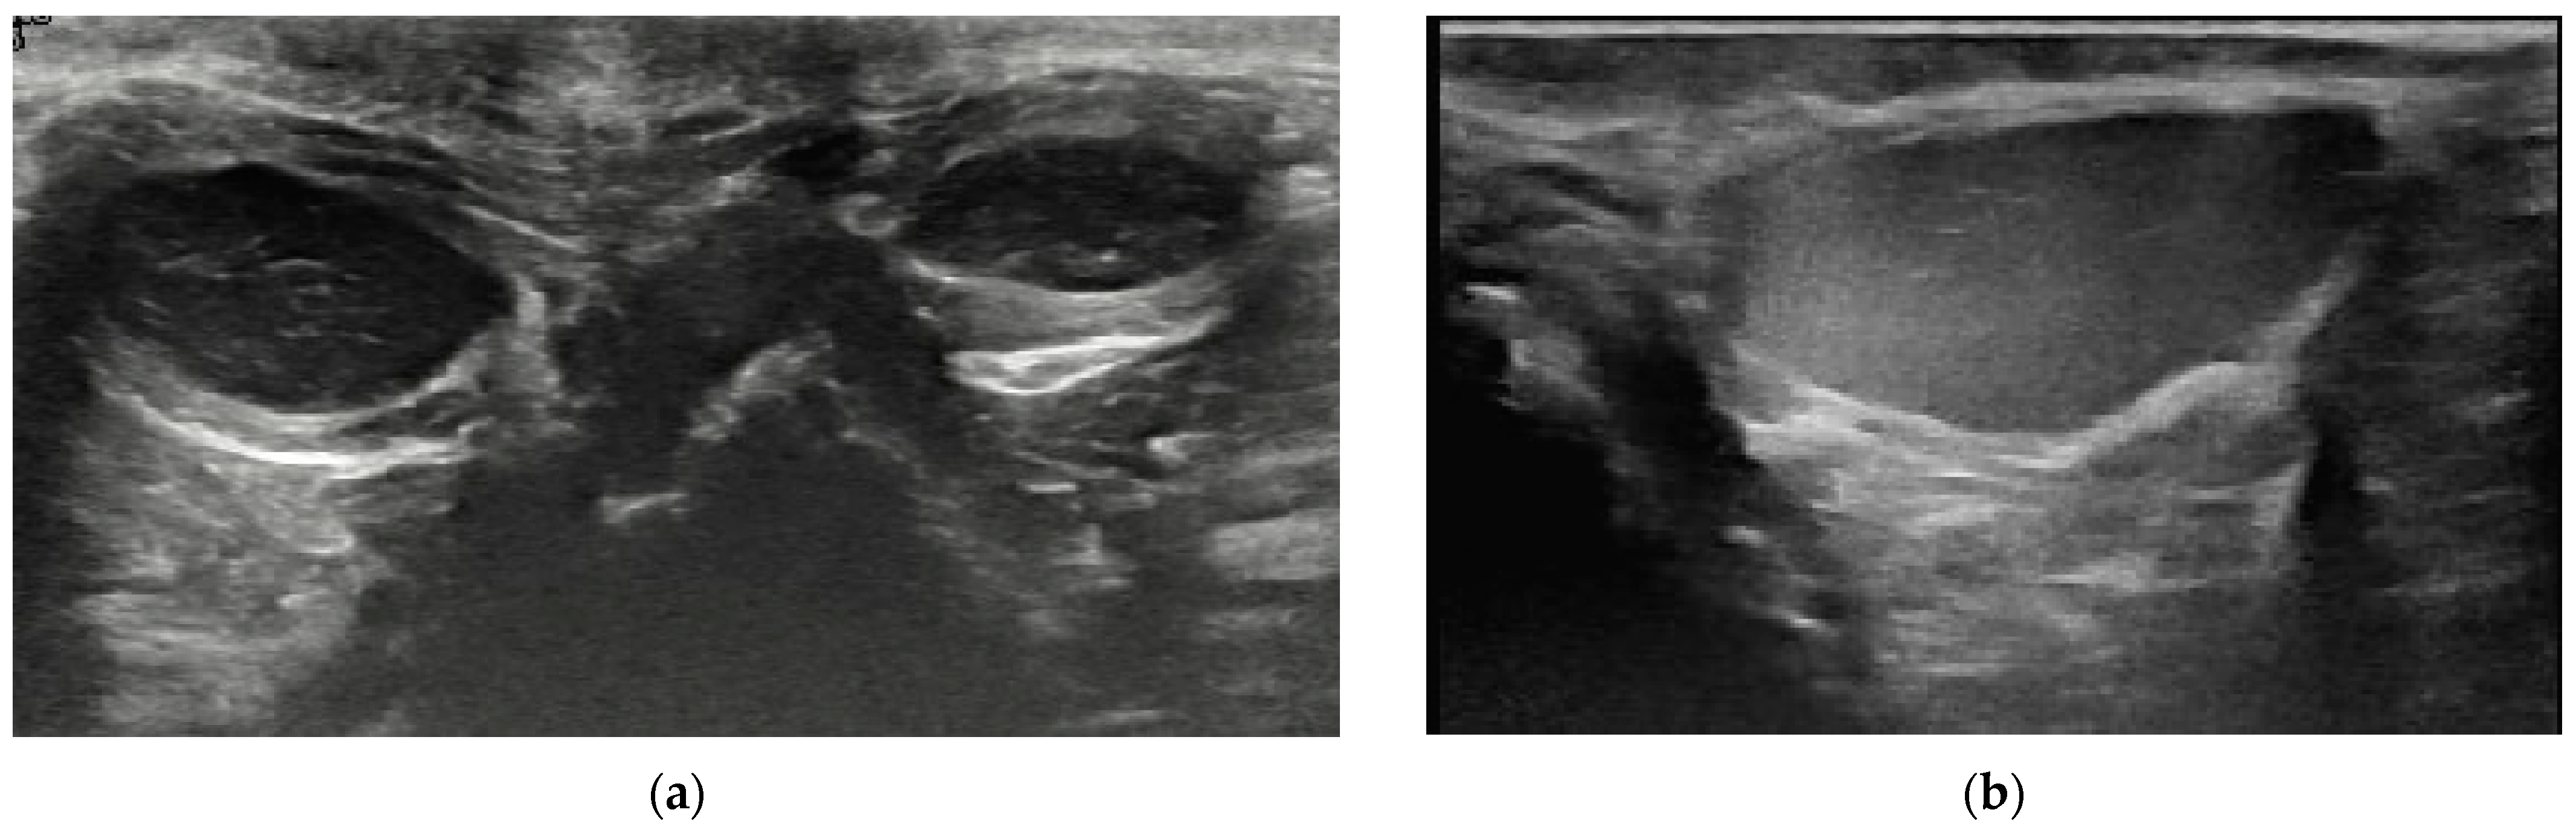

2.4.1. Content of Anal Sacs

3.2. Content of Anal Sacs